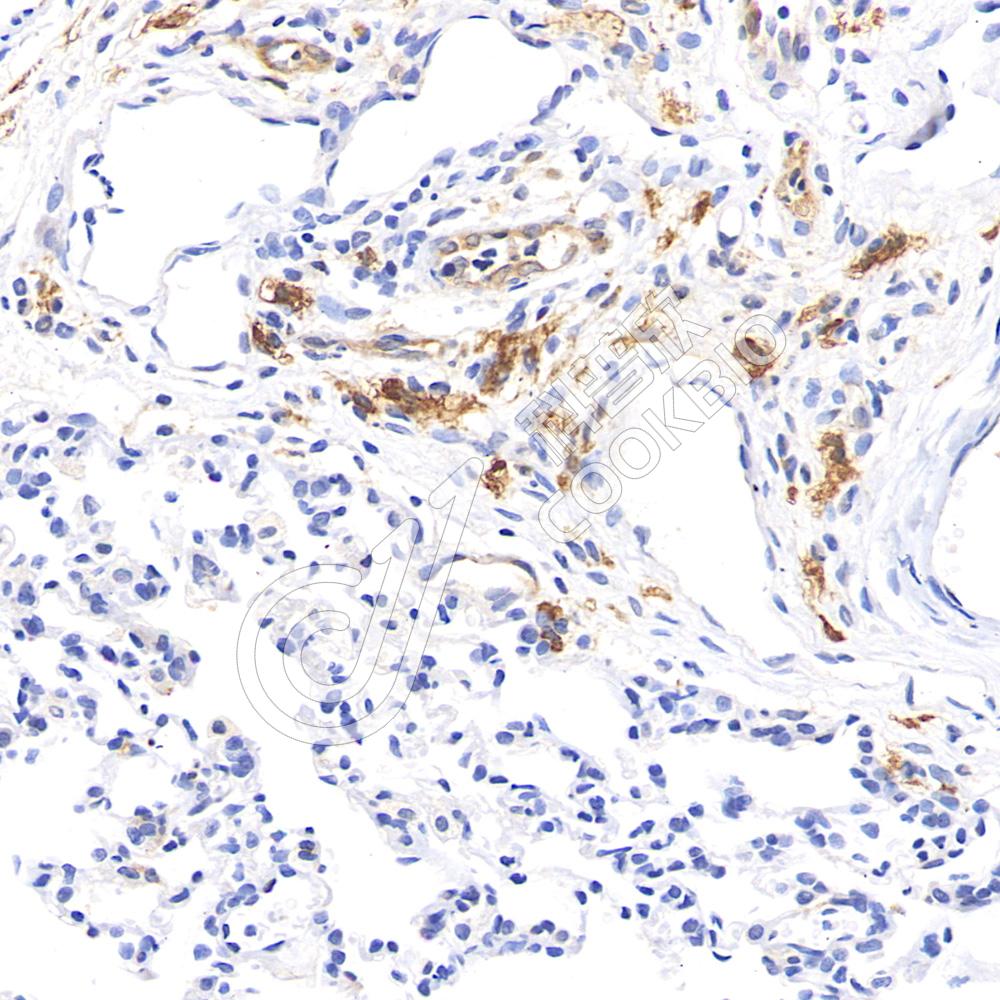

IHC检测CD163蛋白(货号 K1341253).

样品: 小鼠lps(6h)诱导的肺部炎症模型, 4%多聚甲醛 (货号KSG1101) 固定12-24小时.

抗原修复: 柠檬酸抗原修复液(干粉, pH 6.0) (KSG1201), 98℃, 20分钟.

—抗: 1: 800稀释, 4℃ 孵育过夜.

二抗: S-vision免疫组化多聚二抗(山羊抗兔),即用型 (货号KB3906), 室温孵育20分钟.

样品: 大鼠lps(24h)肺诱导炎症模型, 4%多聚甲醛 (货号KSG1101) 固定12-24小时.